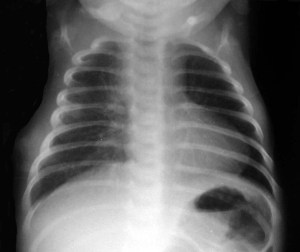

SIGNO DEL CORAZÓN EN FORMA DE ZUECO

Signo de tetralogía de Fallot en la radiografía de tórax. La hipertrofia de la pared del ventrículo derecho provoca un desplazamiento lateral del prominente ápex cardíaco, junto con su afilamiento e inclinación hacia arriba, que confiere a la silueta cardíaca la forma de un zueco con punta redondeada.

Recordemos que la tetralogía de Fallot es una malformación cardiaca congénita que provoca cianosis en el recién nacido. Se asocian una estenosis pulmonar infundibular, una comunicación interventricular, la dextroposición de la aorta y la hipertrofia del ventrículo derecho.

Esta imagen corresponde a otro ejemplo de este signo.